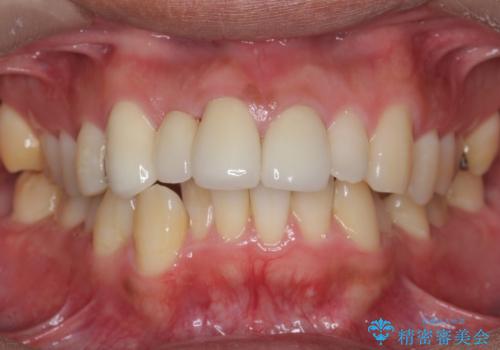

- 78.1万円 内訳(前歯ブリッジ 右上③2➀:ジルコニアクラウンスペシャル15.4万円×3、仮歯1.1万円×3 左上1:精密根管治療再治療 9.9万円×1、ファイバーコア2.2万円、ジルコニアクラウンスペシャル15.4万円、仮歯1.1万円)費用は治療当時の料金となります

右上2番の周りの歯槽骨がかなり吸収が進んでいた影響で、抜歯後そこが大きくへこむことが予想されました。

抜歯後即時にバイオスを詰めることで抜歯後の骨の吸収をなるべく抑える治療(ソケットプリザベーション)を行いました。

歯槽骨が吸収してしまった右上1(隣の歯)との境界については右上1番遠心の歯周ポケットが深いことについては解決できない為、いずれまたダミーの歯の部分に関しては歯肉が下がってしまうことについては説明済みです。

ただ、年齢も鑑みて、直ちに右上12抜歯ではなく、まずは2番のみの抜歯でブリッジにする処置を行いました。